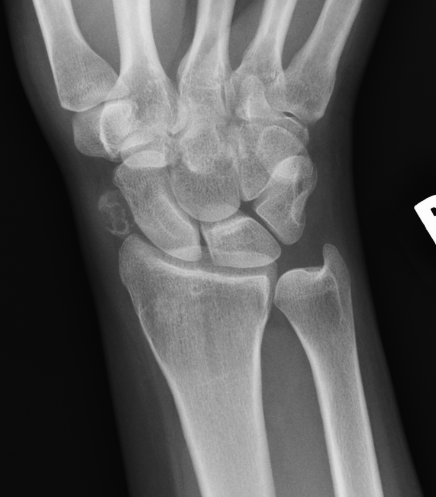

X-ray

Demonstrate calcified lesions / synovial osteochondromatosis

Synovial chondromatosis

Synovial osteochondromatosis

- shoulder > elbow > ankle > wrist

Any synovial lined joint, tendon or bursal cavity